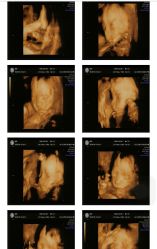

• 郑州万安妇产医院

• -郑州万安妇产医院

相册

小仙女就是Me 上传于 19-01-08 | 报错

莉姐 上传于 19-01-08 | 报错